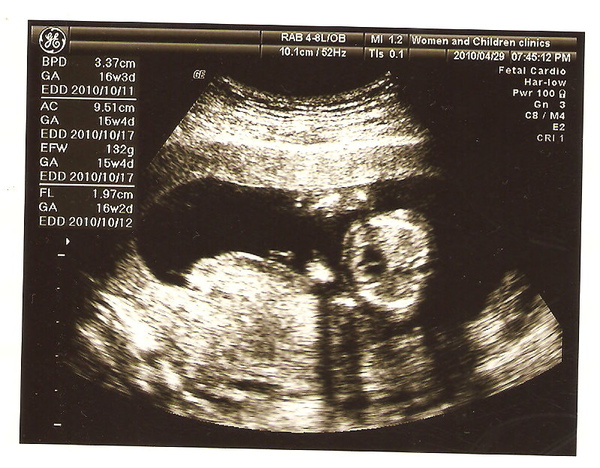

醫生看得很仔細,跟我說小孩子比預產期還大一週,可能需要校正預產期

超音波印出後資料很清楚,郭綜合的超音波照片模糊而且資訊非常的少...

婦兒安螢幕比較大而且超音波清晰很多,加上醫生解說非常詳細又有耐心,我真的考慮要跳槽了...

最後拿到三張照片(真大方,郭綜合只有開始正式產檢後一次一張,上次XX給一張)